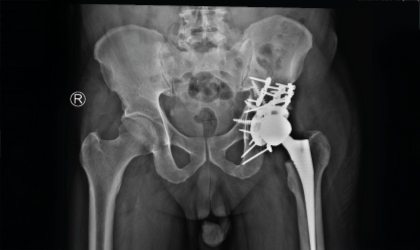

Elderly Hip Fracture Case Study

Complex Hip, Restored

This 62 year old man had a fracture dislocation of his hip following a road traffic accident.